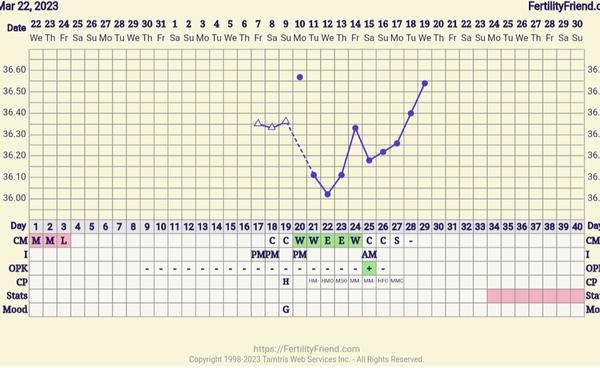

Ahojte, s manželom sa snažíme o dieťa. Začala som si merať bazalnu teplotu. Je pravda ze som začala merať uprostred cyklu, ale rada by som vedela váš názor. Nemala by som mať už potvrdenú ovulaciu? Zdá sa mi, že som mala pred ovu (podľa testu a aj hlienu by mala byť asi 25 DC) príliš vysoké teploty a že po ovu mi nestupa tak ako by mala. Myslíte si, že je to iba tým ze som nemerala cely cyklus a tým pádom sa to nedá vyhodnotiť? Každopádne si chcem sledovať aj ostatné cykly ale príde mi ze nie je všetko v poriadku s tými teplotami 😅

@veronkasim podľa mna ti to vyhodnotí podľa zajtrajšej teploty ☺️Posledný deň nízkych teplôt by mala prebehnúť ovulacia. Pravidlo je, že musíš byt 3 vyššie teploty po sebe, ktoré nasledujú po 6 nízkych, vyššie, ako tie pred ovu. Ak zajtra sa bude držať teplota hore podľa vyhodnotí ovu ☺️